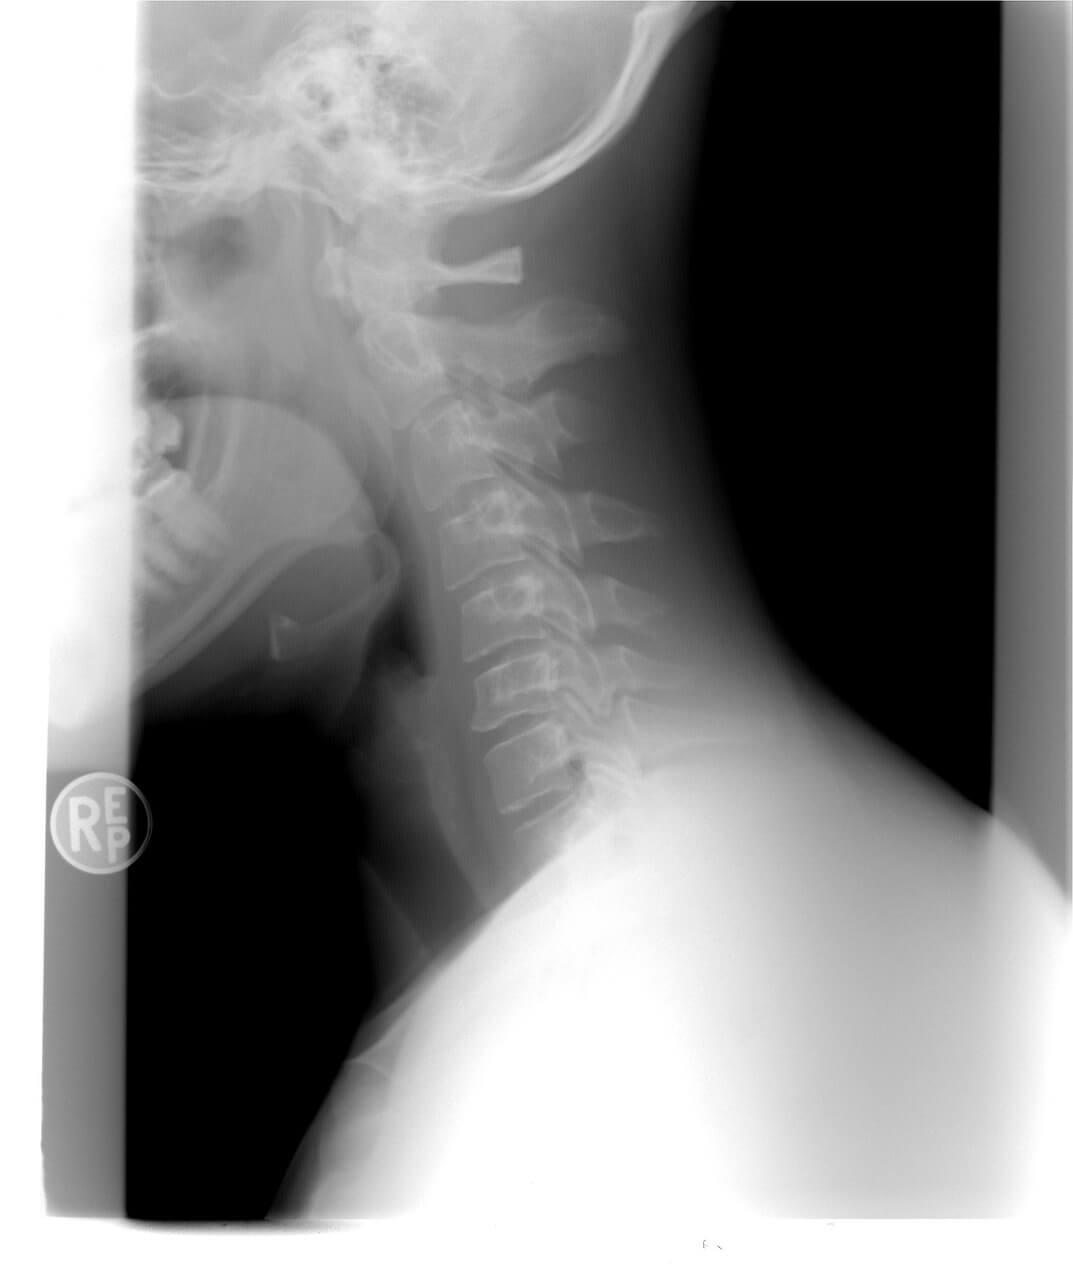

목 디스크란?

경추 디스크라고도 하며 목의 척추뼈 사이에서 충격 흡수 역할을 하는 쿠션과 같은 구조물입니다.

목 디스크는 유연성을 유지하고 목이 부드럽게 움직일 수 있도록 하는 데 필수적인 역할을 합니다.